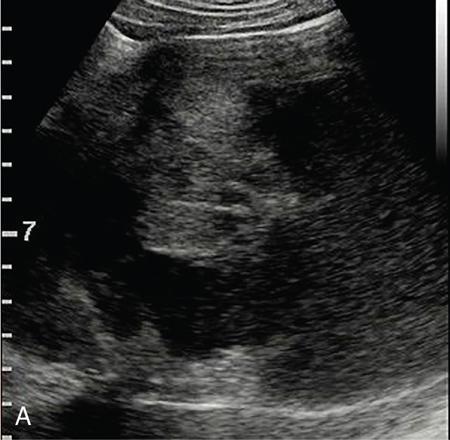

Drushi Patel CONTRAST-ENHANCED ULTRASOUND IN ADULT GENITOURINARY IMAGING Mridula Muthe Ultrasound is the initial screening examination for the evaluation of the renal morphology and suspected renal lesions due to its multiple advantages such as easy accessibility, bedside assessment, affordability and lack of radiation. Vascularity of the kidney and renal lesions can be studied with the use of colour Doppler ultrasound however, it provides information only about the macrovasculature. With the use of microbubble ultrasound contrast agents (UCAs) macro as well as the microvasculature can be studied. Contrast-enhanced ultrasonography (CEUS) is also more sensitive than Doppler ultrasound as it is not affected by blood velocity and angle of insonation of the ultrasound beam. In urology, the established applications of CEUS in adults include characterization of cystic lesions and differentiation between pseudotumours and solid lesions. Box 10.23.1.1 provides a list of European Federation of Societies for Ultrasound in Medicine and Biology (EFSUMB) recommended indications of CEUS in renal evaluation. EUROPEAN FEDERATION OF SOCIETIES FOR ULTRASOUND IN MEDICINE AND BIOLOGY (EFSUMB) RECOMMENDED INDICATIONS FOR USE OF UCA IN RENAL EVALUATION Renal ischaemia. Evaluation of solid renal lesions. Differentiation between solid renal lesions and pseudotumours. Characterization of complex cystic masses. Characterisation of indeterminate renal masses. Renal infections. Follow-up of nonsurgical complex masses. To improve lesion visualization in patients undergoing renal tumour ablation under US guidance and to detect residual tumour either immediately or after ablation. Isolated blunt moderate-energy renal trauma. Follow-up of trauma patients managed conservatively. Characterization of thrombus in renal vein and inferior vena cava. In patients with contraindications for CT- and MRI-based contrast media. Evaluation of lesions in transplant kidneys. Evaluation of ischaemia and vascular complications in transplant kidneys. Tumour response assessment to biologic therapy. Intracavitary CEUS for guiding percutaneous nephrostomy. Source: P.S. Sidhu, V. Cantisani, C.F. Dietrich, O.H. Gilja, A. Saftoiu, E. Bartels, et al., The EFSUMB guidelines and recommendations for the clinical practice of contrast-enhanced ultrasound (CEUS) in non-hepatic applications: update 2017 (long version). Ultraschall in der Medizin-Eur. J. Ultrasound 39 (02) (2018) e2–e44. CEUS involves the intravenous injection of UCAs consisting of gas microbubbles. These UCAs remain purely in the intravascular compartment as they are small enough to avoid filtration by the lungs and too large to enter the interstitial compartment. UCAs cause marked amplification of signals from the flowing blood, thus providing information about the microvasculature and parenchymal perfusion. Sonovue is a second-generation UCA and is the only UCA available in India. It consists of sulphur hexafluoride gas which is exhaled by the lungs and is surrounded by phospholipid monolayer which is metabolised by the liver, making it safe for patients with renal insufficiency. For renal evaluation, a dose of 1–1.5 mL of Sonovue is administered as a bolus dose followed by a 10 mL saline flush. CEUS is performed on machines with contrast-specific software’s using a low mechanical index (MI) technique. The use of a dual image display is beneficial for the evaluation of small lesions. A conventional B-mode ultrasound is first performed to acquire measurements, assess morphology and to detect focal lesions along with Doppler ultrasound to assess vasculature. However, due to limitations in the assessment of focal lesions, microvasculature, complex cysts, poor contrast between the lesion and cortex or medulla, it is preferable to perform a CEUS study for additional characterization. The enhancement pattern of the kidney is different than that of the liver due to the dual blood supply of the liver as opposed to afferent arterial supply and efferent venous drainage of the kidney. After an intravenous bolus of UCA, kidneys show intense enhancement. Contrast is first seen in the main renal artery, followed by its branches. CEUS has only two enhancement phases, that is cortical phase which lasts for 15–30 seconds and a parenchymal phase (enhancement of both cortex and medulla) for 25 seconds–4 minutes after UCA administration. The renal cortex enhances first, followed by the outer medulla which is followed by gradual enhancement of the pyramids (Fig. 10.23.1.1). During the washout phase first, there is a reduction in the medullary enhancement followed by a slower washout of the cortex. As kidneys don’t excrete UCAs, there is no opacification of the pelvicalyceal system. UCAs can act as a problem-solving tool in patients with renal failure as they are not nephrotoxic. Due to its excellent ability to depict renal vascularization, it can be used for detecting perfusion abnormalities. CEUS is useful for detecting vascular causes of renal function deterioration. Renal infarcts appear as wedge-shaped nonenhancing areas in all phases. Renal infarcts show a focal complete lack of parenchymal enhancement on CEUS whereas ischaemic areas show reduced enhancement. CEUS can confidently differentiate infarction from cortical necrosis by the demonstration of preserved hilar vascularity in the latter. Renal pseudotumours such as foetal lobulations, dromedary hump, parenchymal hypertrophy due to renal scarring and column of Bertini can be accurately differentiated from true tumours using CEUS. Pseudotumours show similar enhancement to the adjacent parenchyma and appear isoechoic on all phases while true tumours show different enhancement pattern on at least one phase (Fig. 10.23.1.2). True tumours will cause mass effect and distort the normal vascular architecture of the renal parenchyma whereas in pseudotumours the vascular architecture is preserved. In addition, the identification of medullary pyramids within the mass points towards it being a pseudotumour rather than a true mass. Cysts can be categorized according to the Bosniak classification using CEUS. Due to its superior spatial and temporal resolution, CEUS is considered superior to CT for detecting additional septations, wall or septal thickening and solid components (Figs 10.23.1.3–10.23.1.5). CEUS allows for real-time imaging of blood flow within the septae, wall or nodules within the cysts which may not be seen on CT or MR imaging. The sensitivity of CEUS is comparable to CT for the classification of renal cystic lesions as benign or malignant however, it is not as useful for staging. The follow-up of inoperable complex cystic lesions is better performed with CEUS rather than CT due to the absence of ionizing radiation. Complex cysts or masses with calcifications are not suitable for evaluation with CEUS. CEUS allows a detailed evaluation of the circulation in mass lesions as it demonstrates the macro as well as microvascular enhancement patterns. CEUS has more sensitivity than CT for detecting blood flow in hypovascular lesions. It can also be used to distinguish between complex cysts and solid lesions which remain equivocal on CT and ultrasound (B-mode and colour Doppler). CEUS is sensitive in identifying cystic areas, necrosis, debris and haemorrhage in small tumours that may be difficult to visualize on CECT and MR. Isoechoic lesions on conventional ultrasound are better characterized by CEUS (Fig. 10.23.1.6). Hyperdense renal lesions on noncontrast CT (NCCT) with HU values between 20 and 70 are better evaluated by CEUS which can classify these lesions as solid or cystic. CEUS can suggest the histological subtype of tumours. Clear cell carcinomas show heterogeneous hyperenhancement in the cortical phase and rapid washout along with a peripheral enhancing rim or pseudocapsule seen during the parenchymal phase. Papillary carcinoma shows progressive heterogeneous enhancement during the cortical phase and displays hypoenhancement as compared to the cortex on all phases. Malignant renal vein thrombus will show enhancement as compared to bland thrombus on CEUS. Tumours that are smaller than 3 cm commonly show homogeneous enhancement, regardless of their histologic subtype. Differentiation between angiomyolipoma, renal cell carcinoma and oncocytoma is not always possible. Although, CEUS has excellent sensitivity for the detection of malignancy, it has a higher false-positive rate as compared to CECT. Hence, combined use of CEUS for its high sensitivity and CECT for its high specificity may be performed for an accurate diagnosis. CEUS is effective in patients with complicated pyelonephritis, for identifying inflammatory parenchymal involvement, characterized by round or wedge-shaped hypovascular parenchymal areas, most conspicuous during the late parenchymal enhancement phase. An abscess is seen as a nonenhancing area, with or without peripheral or septal enhancement. CEUS can also be used for the follow-up of renal abscesses. All the aforementioned indications of CEUS in native kidneys also apply to renal transplants. Infarction, vascular complications such as arterial and venous thrombosis can be detected. Quantitative CEUS for assessment of graft dysfunction is a subject of active research. CEUS can be used as an alternative to CT especially in children with isolated blunt moderate energy injuries who are hemodynamically stable. It can also be used in the follow-up of conservatively managed trauma patients and in renal impairment. During Focused Assessment with Sonography for Trauma (FAST), the examination should begin with the kidneys as they have a fleeting enhancement. The kidneys are studied in the arterial phase with two separate doses administered for either kidney during FAST. On CEUS, lacerations, hematomas, and infarcts are seen as nonenhancing areas on late-phase images whereas contusions may show faint enhancement. Pseudoaneurysms and active bleeding are diagnosed on the arterial phase. Crucial complications such as devascularized parenchyma and acute cortical necrosis can also be diagnosed on CEUS. Pelvicalyceal system injury cannot be detected by CEUS as UCAs are not excreted by the kidneys. CEUS can be performed in conjunction with percutaneous ablation therapies. Preablation evaluation with CEUS is essential to assess lesion vascularity and to compare pre and postprocedure tumour viability. Also, the identification of a pseudocapsule predicts improved ablation efficacy. CEUS has demonstrated high sensitivity, specificity and accuracy for the early detection of residual unablated tumour. Dynamic contrast-enhanced ultrasound is a useful tool for early identification of responders and nonresponders, enabling tailoring of the treatment regimen. It is performed by two methods – Bolus injection of a UCA with time-intensity curve analysis (commonly used) and intravenous injection of UCA with disruption–replenishment analysis. In patients with chronic kidney disease, the contrast enhancement is less intense and fades earlier as compared to a normal kidney. CEUS aids in characterizing renal lesions in patients with renal failure. Characterization of lesions with indeterminate appearances in patients with renal dysfunction, on conventional US prevents unnecessary further evaluation with contrast-enhanced CT or MRI and further deterioration of the renal function as well as unwarranted investigations. CEUS nephrostomogram can be performed after percutaneous nephrostomography to confirm the correct positioning of its tip, detect the site of obstruction and to diagnose complications. UCAs can be safely administered in patients with minimal risk. They can be safely administered in patients with renal insufficiency as they are not excreted by the kidneys. Prior laboratory tests are not indicated as they are not nephrotoxic and don’t interact with thyroid function. Most adverse effects are mild such as nausea, headache, chest discomfort, chest pain and resolve spontaneously. The contraindications include known hypersensitivity, patients with right-to-left shunts, severe pulmonary arterial hypertension (pulmonary arterial pressure >90 mm Hg), uncontrolled systemic hypertension, and respiratory distress. The rate of anaphylactic reactions is significantly lower than iodinated contrast media and comparable to gadolinium-based contrast agents. Caution should be exercised in patients with severe acute coronary disease and in patients with unstable angina. CEUS is a rapidly evolving technique, can be conveniently performed as an extension of conventional ultrasound and acts as a valuable tool in the characterization of indeterminate renal lesions, especially when the lesion is small. The advantages of CEUS include quick assessment, real-time imaging, high contrast resolution, excellent safety profile, lack of ionizing radiation, great repeatability, and most importantly, ideal for contrast evaluation in patients with deranged renal function. DUAL-ENERGY AND SPECTRAL IMAGING IN GENITOURINARY SYSTEM Aditi Chaitanya Gujarathi-Saraf Dual-energy CT (DECT) also known as ‘spectral imaging’, was first conceptualized in the 1970s. However, the clinical applications of DECT have recently emerged as owing to improvements in postprocessing techniques. The development of a single-detector, single-source DECT (ssDECT) with the capability for rapid alternation between two peak voltage settings (‘fast switching’) and a dual-detector, dual-source DECT (dsDECT) system in last few years have made possible various applications in solving clinical problems. In DECT, the simultaneous use of two different X-ray beam energy settings (80 and 140 kVp) allows the differentiation of materials on the basis of their attenuation characteristics (material density). There are two major applications of DECT in genitourinary system. First being characterization of renal calculi to differentiate those containing uric acid (UA) from those which do not. The other application is to characterize small renal masses which include differentiating complex cysts from renal tumours, detection of solid growth in PCKD patients and detection of residual tumour after thermal ablation of a renal neoplasm. The principle of DECT imaging is based on the differential absorption of X-ray energy at variable kVp settings. In DECT, two energy levels (typically 80 and 140 kVp) are used to acquire images that can be processed to generate additional datasets. Thus, a tissue or any material in the body shows different degrees of attenuation when scanned at different X-ray energies. Conventional CT numbers (attenuation measurements in Hounsfield units) are related to the linear attenuation coefficient of a particular material. The unique linear attenuation coefficients obtained by imaging at two different energies can be used to discriminate between different materials (e.g. fat, calcium, iodine and water). The characterization of material on DECT depends on their CT number ratio (CTR) also called dual-energy ratio. DE RATIO = CT number of a given material in the low-energy image CT number of the same material in the high-energy image DECT and spectral CT can be performed by three techniques (Fig. 10.23.2.1): Two sets of material-specific images are created to detect the presence or absence of a material. The two basic materials selected should have significant difference in mass attenuation coefficients and atomic number. The two commonly selected pairs are: Iodine-specific images are most commonly used in the clinical practice. When iodine is paired with water, two separate image data sets are generated. On water density image, the voxels that show change in attenuation due to presence of iodine are removed. These are instead represented on iodine density images. Thus, virtual unenhanced images are generated which resemble the conventional unenhanced images. Renal calculus disease is a common disease affecting approximately 10%–14% of population in India commonly affecting 31–45-year-old patients. Accurate diagnosis of composition of renal calculi is crucial as the frequency of prevalence and recurrence rate of renal calculi is high in most states of India. The obstructing calculi can lead to obstructive uropathy, pyelonephritis, urinary sepsis with nearly 50% of the patients being affected by renal failure. There are multiple compositions of renal calculi, most common being calcium oxalate (70%), calcium phosphate (20%), uric acid (8%) and cystine (2%). In general, UA calculi have lower attenuation values than nonuric acid calculi (i.e. struvite, cystine and calcium) on conventional CT. However, it may be difficult to distinguish between the two due to overlap in attenuation values. Here DECT becomes a problem-solving tool as it uses the two-material differentiation approach. Thus, in addition to size and location, DECT provides information about the composition of calculi to the urologist. DECT has high sensitivity of 88%–100% and high accuracy of 93%–100% to differentiate UA calculi from nonuric acid UA calculi. This is of utmost clinical importance as UA calculi can be treated medically whereas non-UA calculi require invasive methods of treatment such as extracorporeal shockwave lithotripsy (ESWL) or percutaneous nephrolithotripsy (PCNL). In clinical practice, NCCT scan of KUB region is performed at 80 and 140 kVp to generate two image datasets and obtain the DE ratio. A cut-off value of DE ratio of 1.2 is used to differentiate UA calculi from non-UA calculi (Fig. 10.23.2.2). Following flow chart shows differentiation of renal calculi based on DE ratio.